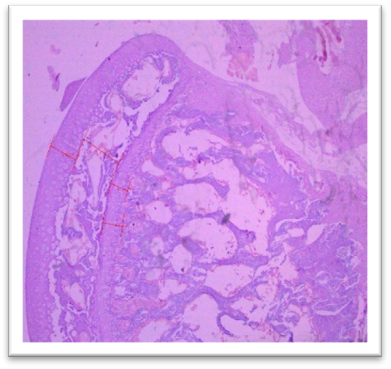

Histomorphometry

At the end of the study, femur bones were dissected and fixed for histological analysis. Group I (Normal) showed normal bone architecture, with well-organized chondrocytes. Group II (Lanthanum Carbonate only) maintained normal bone growth. Group III (Chronic Kidney Disease control) exhibited fibrocartilaginous changes, disorganized collagen, and impaired endochondral ossification, characteristic of Chronic Kidney Dosease. Groups IV (150 mg/kg), V (250 mg/kg), VI (500 mg/kg), and VII (750 mg/kg) demonstrated varying degrees of improvement in bone structure, with the highest dose (Group VII) showing the most significant restoration of normal bone architecture. Histomorphometry of bone: In Group III, designated as positive control for Chronic Kidney Disease, histomorphometric analysis of femur revealed significant fibrocartilaginous changes within the articular cartilage, characterized by an increased fibroblast, loss of chondrocyte organization, and disorganized collagen deposition. Furthermore, the growth plate exhibited a marked increase in the thickness of the hypertrophic zone, suggesting impaired endochondral ossification. Similar findings were observed by Saito et al. (2021) who observed that in Adenine-induced Chronic Kidney Disease, there was a reduction in bone minera density (BMD) throughout the body as well as in the femur Furthermore, micro- computed tomography (micro-CT) analysis revealed a decline in the microstructural integrity of the cortical bone, which contributed to diminished bone strength in both cortical and trabecular regions. Ferrari et al. (2014) reported that the bone microarchitecture in rats subjected to Adenine-induced renal failure exhibited significant alterations, characterized by a reduced trabecular number and an increased trabecular separation. Additionally, the presence of fibrosis was noted in the rats with Adenine-induced renal failure. Ni et al. (2018) performed a histomorphometry analysis and revealing that the bone mineral density (BMD) in the femurs of rats with Chronic Kidney Disease (CKD) was markedly lower than that observed in the control (CTL) group. Additionally, significant bone loss was evident in both cortical and trabecular bone parameters of the femurs.  Lanthanum Carbonate @150mg/kg, 250mg/kg, 500mg/kg and 750 mg/kg, histomorphometric analysis revealed very minimal to nearly absent fibroblast proliferation in the articular cartilage, characterized by the absence of fibroblast- like cells and well-maintained chondrocyte organization. Additionally, the growth plate exhibited moderate proliferation of the hypertrophic zone, indicating significant improvement in endochondral ossification compared to the positive control group (Group III) and lower-dose treatment groups. These findings suggest that the highest dose of Lanthanum Carbonate (750 mg/kg) may provide the most effective therapeutic benefits in mitigating bone-related pathological changes associated with Chronic Kidney Disease Yajima et al. (2018) demonstrated that Lanthanum Carbonate enhanced the mineralization of the periosteal surface, augmented bone mass within the intracortical resorption areas, and improved mineralization on the minimodeling surface at the endocortical region. They concluded that Lanthanum Carbonate has the potential to bolster cortical stability in patients with Chronic Kidney Disease (CKD)..

Fig. 26 Group III femur, showing fibrocartilaginous changes, fibroblasts, loss of chondrocyte organization, and disorganized collagen deposition at articular cartilage. Increased thickness of the hypertrophic zone in the growth plate